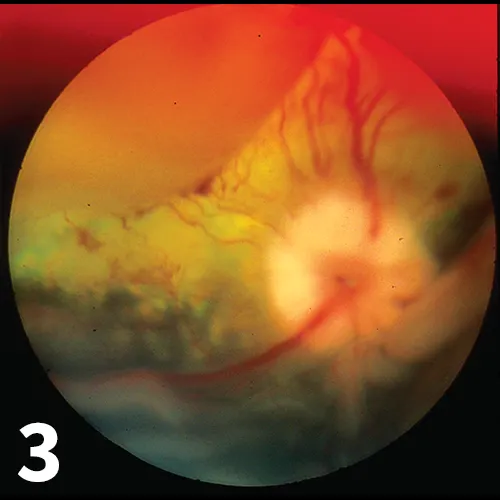

Figure 3

Photograph of the fundus of a dog utilizing a condensing lens for indirect ophthalmoscopy. RD and intra- and subretinal hemorrhage are demonstrated. Note the different planes of focus, the indistinct margins of blood vessels, and the prominent dorsal and ventral partial detachments. These conditions were secondary to acute kidney disease and systemic hypertension in this patient.

Diagnosis of RD is made during a thorough ophthalmic examination that includes either direct or indirect ophthalmoscopy. RD will appear either as a thin grey veil of tissue with visible blood vessels or as a hyporeflective section of the fundus with indistinct or fuzzy margins on ophthalmoscopy. Retinal blood vessels may be observed in different planes of focus depending on how far forward they have been displaced (Figure 3).